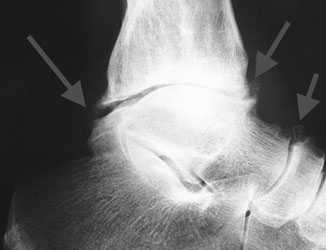

Не смотря на то, что Loomer с соавт. сообщили, что только от 50% до 66% остеохондральных дефектов обнаруживаются при помощи обычной рентгенографии, данный метод является важной отправной точкой и может быть полезен для исключения другой патологии голеностопного сустава [20]. Рентгенологическое исследование голеностопного сустава должно включать переднюю, заднюю и в 3⁄4 внутренней ротации проекции. Все проекции выполняются стоя (под нагрузкой) и называются функциональными. Функциональные рентгенограммы могут быть полезны для выявления сопутствующей нестабильности голеностопного сустава, проекция 3⁄4 во внутренней ротации, помогает в визуализации щели межберцового синдесмоза, а так же отображает передне-внутрений импижмент (таранной и большеберцовой кости) в случае его наличия. Выполненные в положении подошвенного сгибания прямая и 3⁄4 проекция во внутренней ротации могут быть полезны в выявлении заднемедиального поражения таранной кости. Рентгенологические признаки, которые могут быть определены, варьируются от небольших участков сдавления субхондральной кости до крупных отслоенных остеохондральных фрагментов. Радиографическая

система классификации была разработана Berndt и Harty в 1959 году и остается золотым стандартом. (Табл. 1) [16]. Loomer с соавторами дополнили имеющуюся классификацию, на основе не только рентгенограмм, а также МРТ (магнитно-резонансная томография) и КТ (компьютерная томография), и добавили стадию V в систему классификации Berndt и Harty [22].

а. рентгенограмма голеностопа. - КТ. Метод, позволяющие понять, какую структуру имеют остеофиты. Также помогает в обнаружении патологии на начальной стадии, когда рентгенологической картины может быть недостаточно для постановки диагноза.

а. на рентгенограммах артроз голеностопного сустава, б. на КТ голеностопного сустава некроз таранной кости.